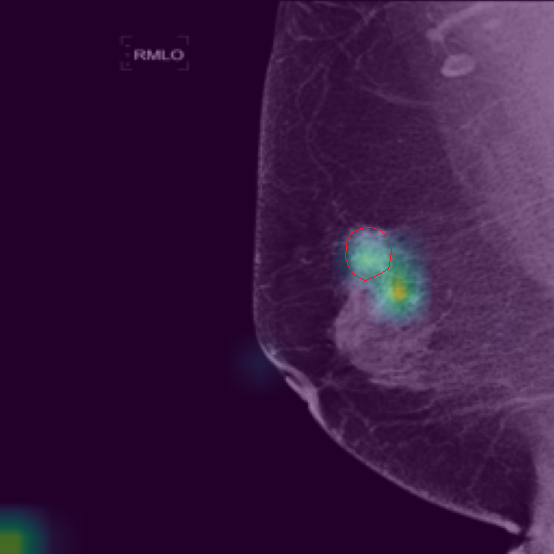

5.9 ViKL Provides Evidence for Clinical Decision

In our earlier sections, we discussed how ViKL enhances the image branch’s capability for detailed feature extraction by using text and manifestations that describe localized lumps. To directly observe this enhanced feature extraction ability, we utilize the class activation map (CAM) [62], a common tool for visualizing neural network activations. Specifically, we employ Grad-CAM [63] to generate activation maps from the third layer of the ResNet50 model, which has been fine-tuned using ViKL on the MKVL dataset. Additionally, for accurate visualization and comparison, we include markings of lumps as annotated by professional radiologists. The results of this visualization are showcased in Fig. 6. These visualizations demonstrate ViKL’s effective localization of small lesions, highlighting its refined ability to capture minute features in medical imaging.